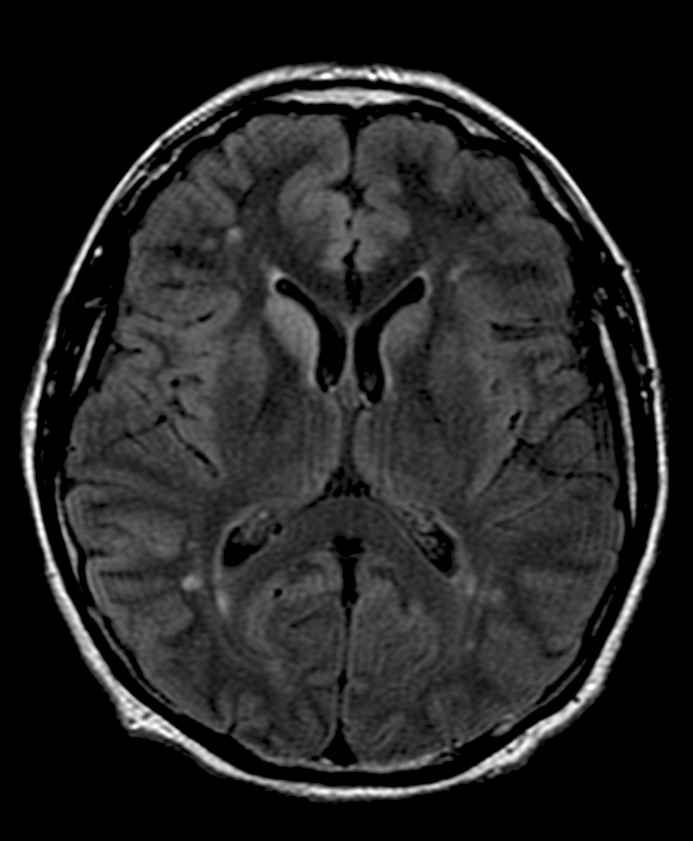

Paciente de 48 años con demencia rápidamente progresiva.

- D. Enfermedad de Creutzfeldt-Jacob con alteración de señal asimétrica en núcleo caudado y cortical frontotemporal.

- B. FLAIR.